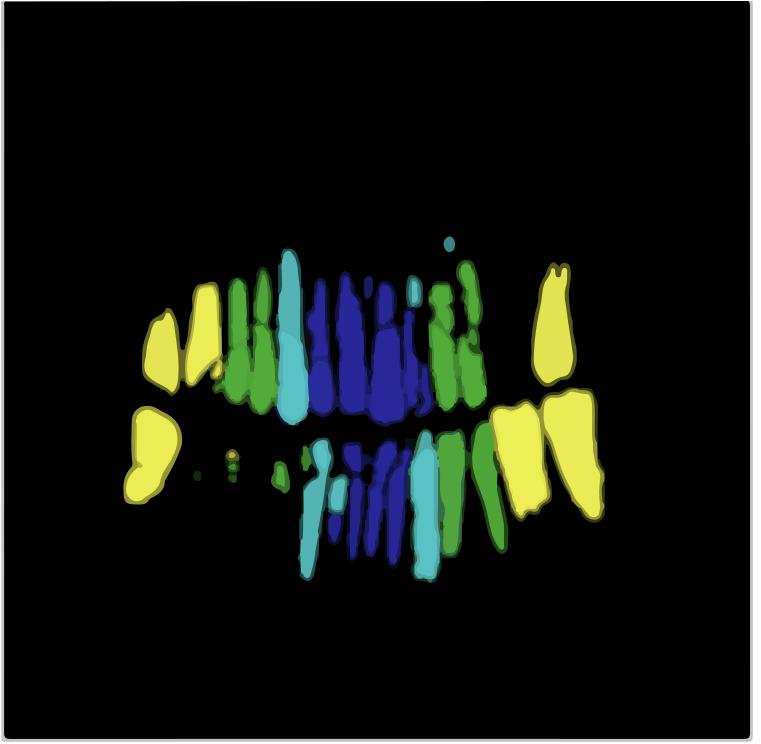

Due to the lack of image labels necessary for training models in the presented dataset, we initially labelled 425 images from the set. We collected two sets of basic annotations, for instance segmentation and object detection respectively. We selected these 425 images randomly from all categories and maintained same distribution of images across all categories as in the original dataset. For manual labelling, we chose the semi-automated annotation tool Roboflow [28] for bounding box annotations needed for the objection detection task. We also used another annotation tool, Apeer [29], to help us create individual segmentation masks for each of the 32 teeth in the images in the dataset. These binary masks provided additional information by focusing on the fine contours and boundaries of the teeth. We converted the resulting segmented polygons into binary maps of size 512×\times512×\times32. This comprehensive approach to annotation was pivotal in ensuring our model’s success in dental image analysis. An example of annotations is shown in Fig. 2.

Refer to caption

Figure 2: (a) Annotated polygon mask. (b) Annotated bounding Box scan. (c) Binary mask of polygon-based annotation